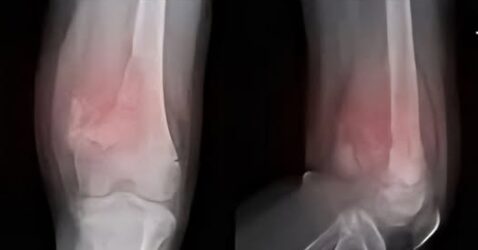

Cáncer de Huesos: Síntomas y Señales de Alerta que No Debes Ignorar.